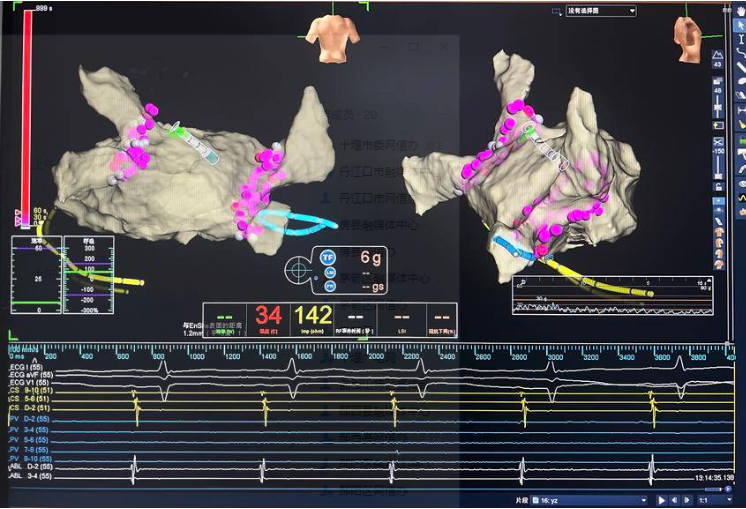

左心耳封堵

隨后,手術(shù)團(tuán)隊乘勝追擊,運用射頻消融技術(shù)進(jìn)行了雙側(cè)肺靜脈前庭及上腔靜脈電隔離,精準(zhǔn)地消除了房顫病灶,恢復(fù)了心臟的正常節(jié)律。緊接著,手術(shù)團(tuán)隊將左心耳封堵器放置到位,鉤掛穩(wěn)定。造影顯示,左心耳封堵完好,未見明顯殘余漏。這一步驟的成功,徹底阻斷了血栓形成的源頭,為朱女士的未來生活提供了有力的保障。